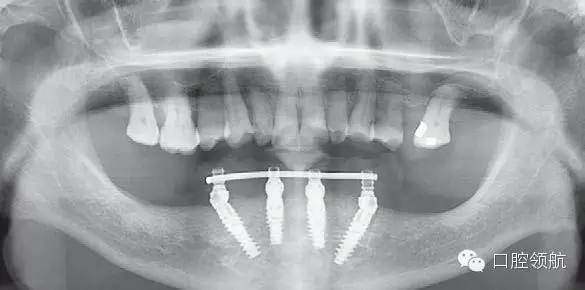

圖6-16為過渡義齒佩戴后的全景片。這張全景片的作用是確認螺絲固位過渡義齒的臨時內冠復合基臺與復合基臺完全就位。如果全景片無法準確確認時,建議拍攝小牙片確認所有的臨時內冠復合基臺就位完好。過渡義齒就位不良,是引起All-on-4種植體早期脫落的一個主要原因。確認就位后開始咬合調整。

圖6-16 下頜All-on-4過渡義齒戴牙后的全景片